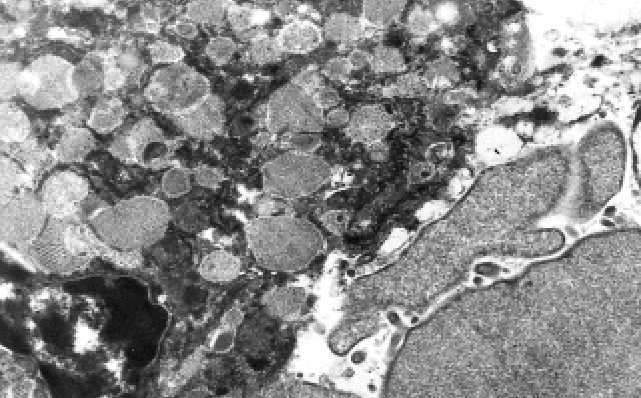

Obr. B.2.7. B. Ultrastrukturálně sklovité hyalinní globule sestávají z amorfní sekrece uvnitř

hrubého endoplazmatického retikula.